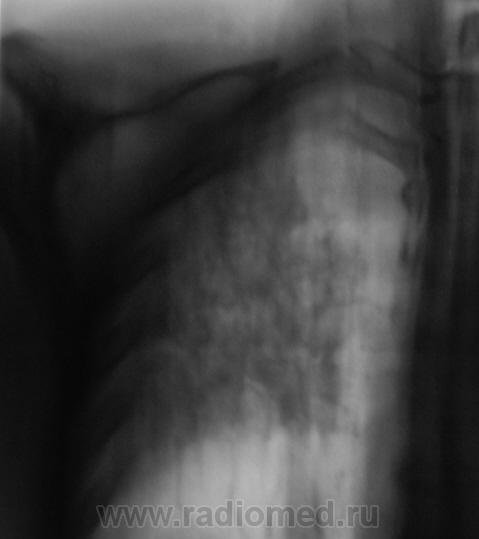

Как всегда, всё началось с "контроля" после флюорографии. Пациента дообследовали согласно стандарту.

Конечно, основная дифференциальная диагностика проводилась между пневмонией и "туберкулёзным поражением".

Но пациент жалоб не предъявляет, клиники - никакой. Коллеги клиницисты - в полной растерянности. Назначили консультацию фтизиатра.

1. Процесс двусторонний.

Вот, и мы так решили, с учетов ограничеснных возможностей нашей ЦРБ-ушки. Взял коллега фтизиатр "изображения", а также и изображения в динамике, а также необходимый "гарнир", и поехал в головное "фтизное" учреждение. В учреждении проконсультировали и выставили правосторонний инфильтративный. Ну и у нас считай - гора с плеч...

Людмила Григолрьевна, но тут, то процесс двусторонний, хоть преимущественно правосторонний. А на полноформатных изображениях (томограммах), и очаги справа в среднем и нижнем легочных полях дифференцировались.